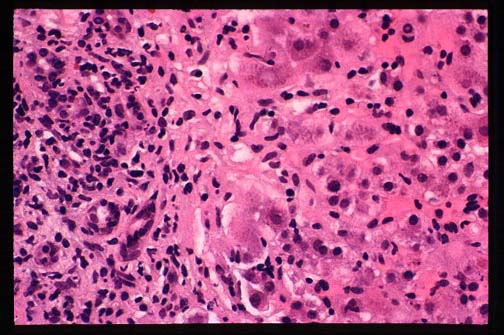

Fig. 9-1-3-Autoimmune hepatitis.

Lobular inflammation and focal necrosis.

Fig. 9-1-4-Autoimmune hepatitis.

Cirrhotic stage. This patient was a 16 year old

girl affected by hepatitis for only 3-4 years.

Notice the macro nodular appearance of the

liver very similar to viral hepatitis.

The vulnerable area affected by autoimmune hepatitis is the periportal region. There is marked portal and periportal chronic inflammation with lymphocyte and macrophages which spill through the limiting plates encircling periportal hepatocytes,("rosetting") which are destroyed,("piecemeal necrosis")."Bile duct lesion"

Connective tissue replaces the lost parenchyma. The portal tract is expanded and assumes a"maple leaf"configuration. Periportal necrosis and fibrosis may extend far rom the portal region and link with an adjacent portal tract forming a bridging necrosis. Cirrhosis may follow. This process is similar to any other chronic active hepatitis. Only the presence of an excessive number of plasma cells and the rosetting phenomenon may indicate an autoimmune process, but their scarcity or absence do not rule out this condition. The histological form of lobular hepatitis especially in relapses is a distinguishing finding from viral hepatitis